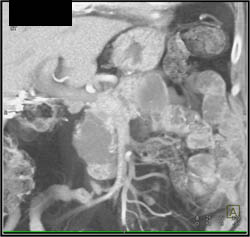

Pancreatic Cancer Encases PV/SMV With Collaterals